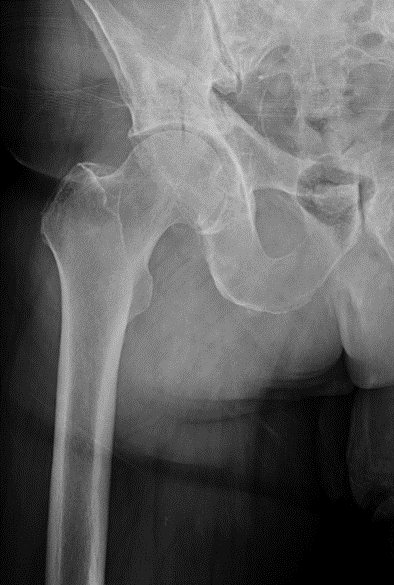

Case presentation: 70 yo F presents to clinic s/p short CMN of left intertroch fx at outside facility in Aug 2022 with worsening left hip pain, inability to bear weight. No pertinent PMHx. Workup and treatment plan?

Infxn workup negative, Lateral approach used, Wagner osteotomy to facilitate nail removal, autograft from femoral/neck 50 cc allograft to graft defect in posterior column, multihole cup/screws w/ dual mobility, modular fluted tapered stem.